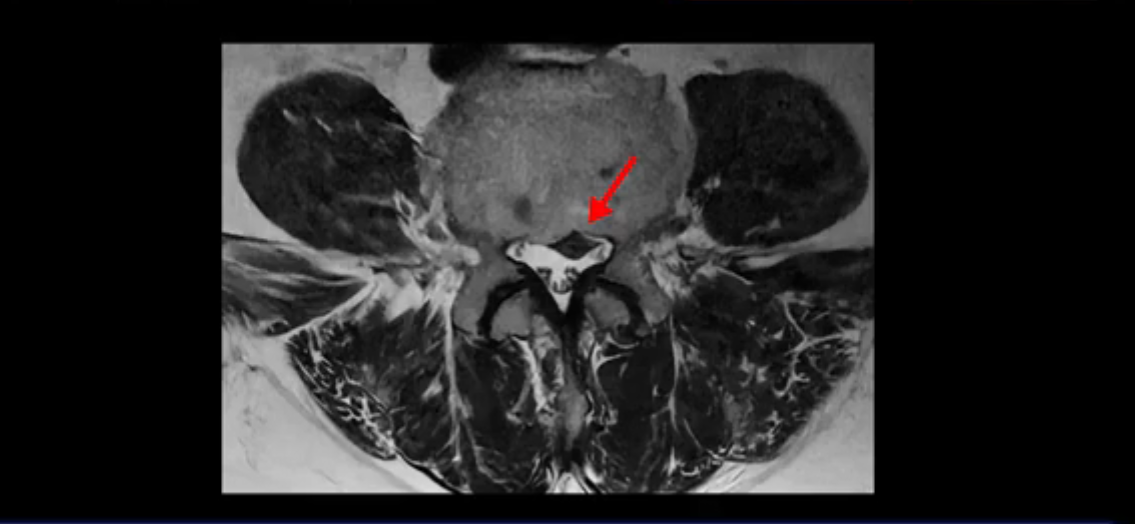

그런데 이분은 4번 5번에도 디스크 파열이 있습니다.

가운데로 심하게 밀려 나와 있는데요.

또 4번 5번에는 협착으로 척추관이 많이 좁아져 있습니다.

또 왼쪽 신경 가지들이 빠져 나가는 신경구멍들이 여러 마디가 좁아져 있습니다.

이런 이유들 때문에 왼쪽 엉덩이부터 종아리, 발가락까지 저리고 아픈 겁니다. 그래서 서둘러 병원에 가셨는데요. 그래서 서둘러 병원에 가셨는데요. 여러분이 꼭 아셔야 할 게 이렇게 다리가 심하게 저리고 아프면 X-ray만 찍을 게 아니고 MRI를 찍어 보시는 게 맞습니다. X-ray로는 디스크가 터졌는지 신경구멍이 좁아진 협착이 있는지를 정확히 할 수가 없습니다. 그래서 이분은 당장 아픈데 해결이 안 되니까 제주도에서 유명하다는 한의원으로 갔습니다.